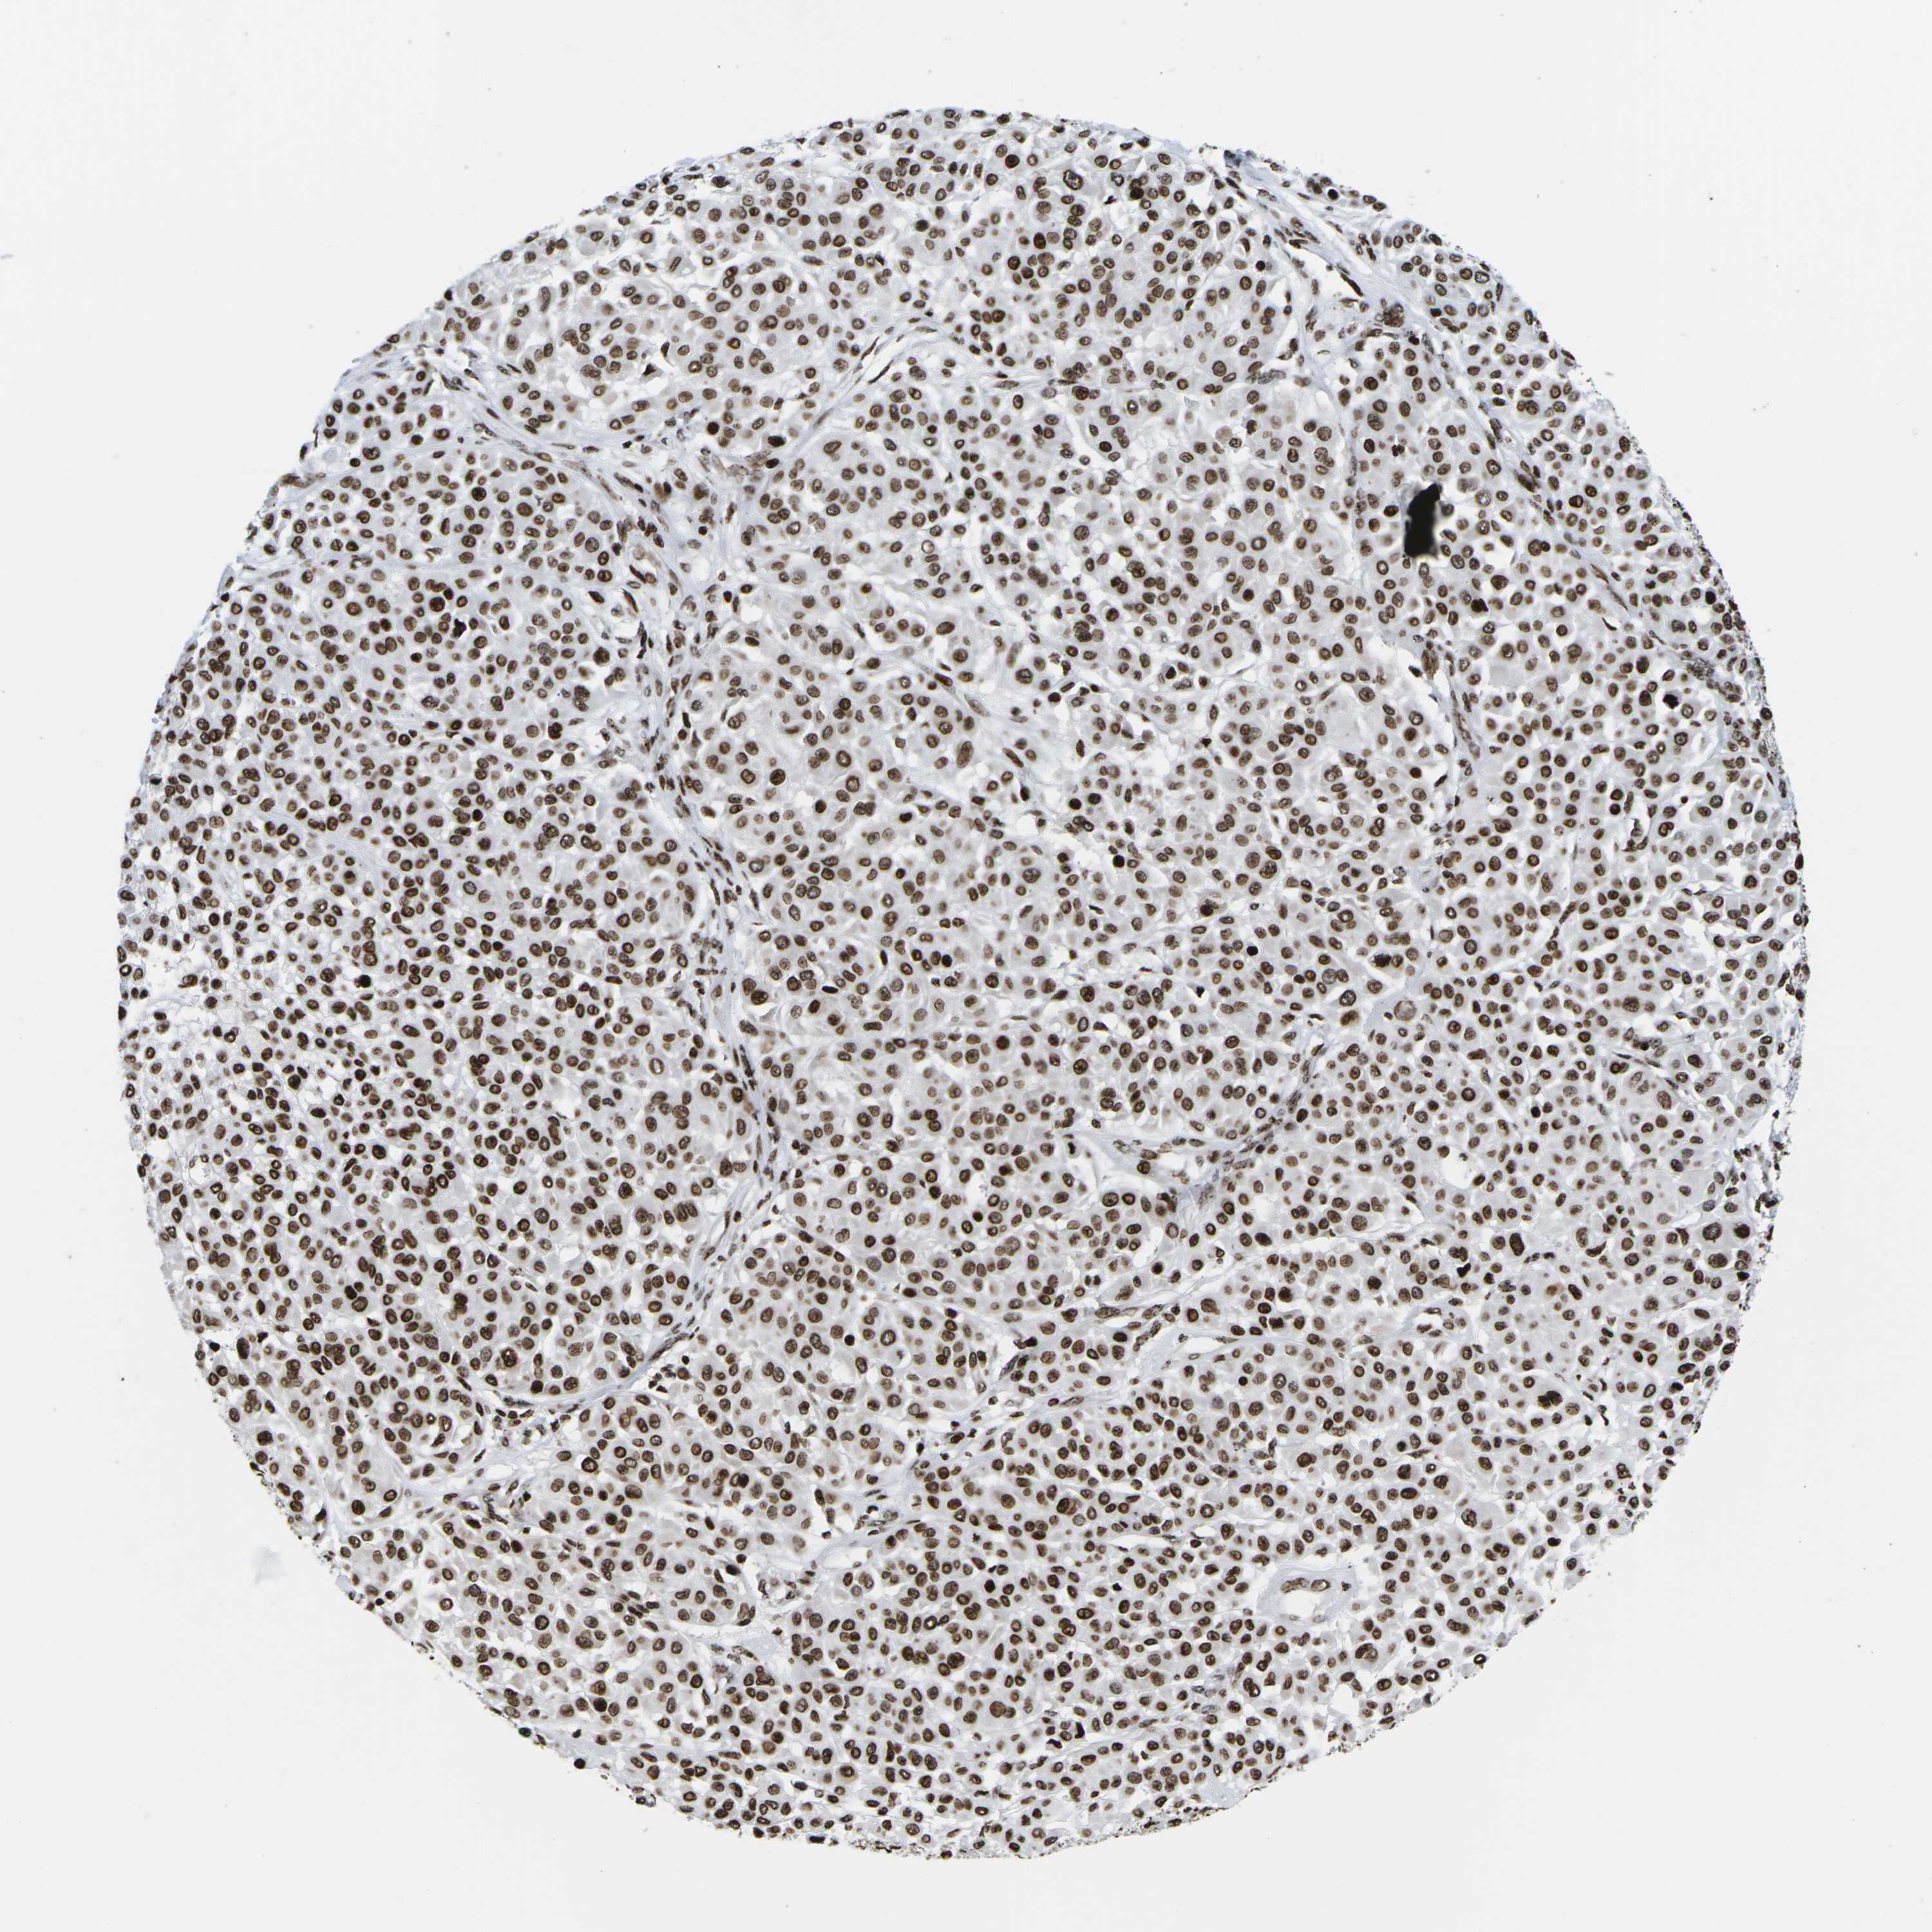

MELANOMA - Protein expressioni

A mouse-over function shows sample information and annotation data. Click on an image to view it in a full screen mode. Samples can be filtered based on level of antibody staining by selecting one or several of the following categories: high, medium, low and not detected. The assay and annotation is described here.

Note that samples used for immunohistochemistry by the Human Protein Atlas do not correspond to samples in the TCGA dataset.

Antibody stainingi

Antibody staining in the annotated cell types in the current human tissue is reported as not detected, low, medium, or high, based on conventional immunohistochemistry profiling in selected tissues. This score is based on the combination of the staining intensity and fraction of stained cells.

Each image is clickable and will lead to virtual microscopy that enables deeper exploration of all samples and also displays staining intensity scores, fraction scores and subcellular localization as well as patient and tissue information for each sample.

Antibody HPA055907

Antibody CAB011506

Staining

High

Medium

Low

Not detected

Intensity

Strong

Moderate

Weak

Negative

Quantity

>75%

75%-25%

<25%

None

Location

Nuclear

Cytoplasmic/membranous

Cytoplasmic/membranous,nuclear

Malignant melanoma, NOS

Malignant melanoma, Metastatic site